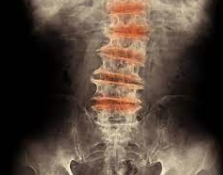

このなかには、強直性脊椎炎、変形性関節症などが含まれています。